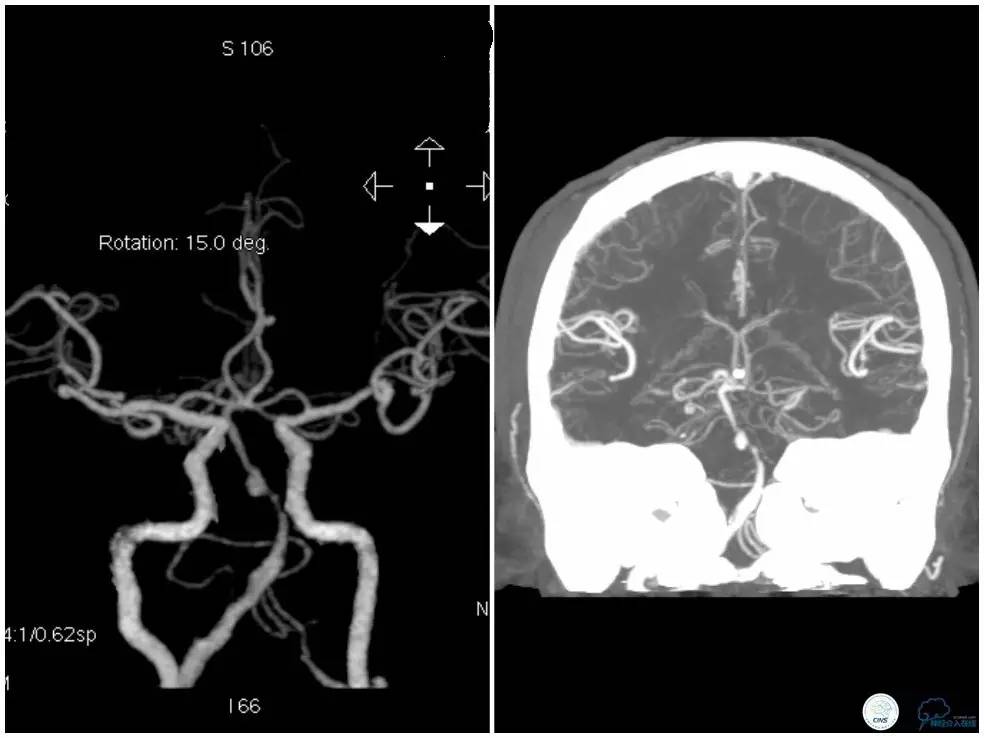

头颈部CTA示基底动脉及右侧椎动脉V4段狭窄,基底动脉狭窄远端局部管腔扩张(图2)。

图2

头颅CTA示(图5):右椎动脉优势、局部狭窄,左侧椎动脉细、狭窄;基底动脉迂曲,起始处狭窄,中部可见突起影。

图5